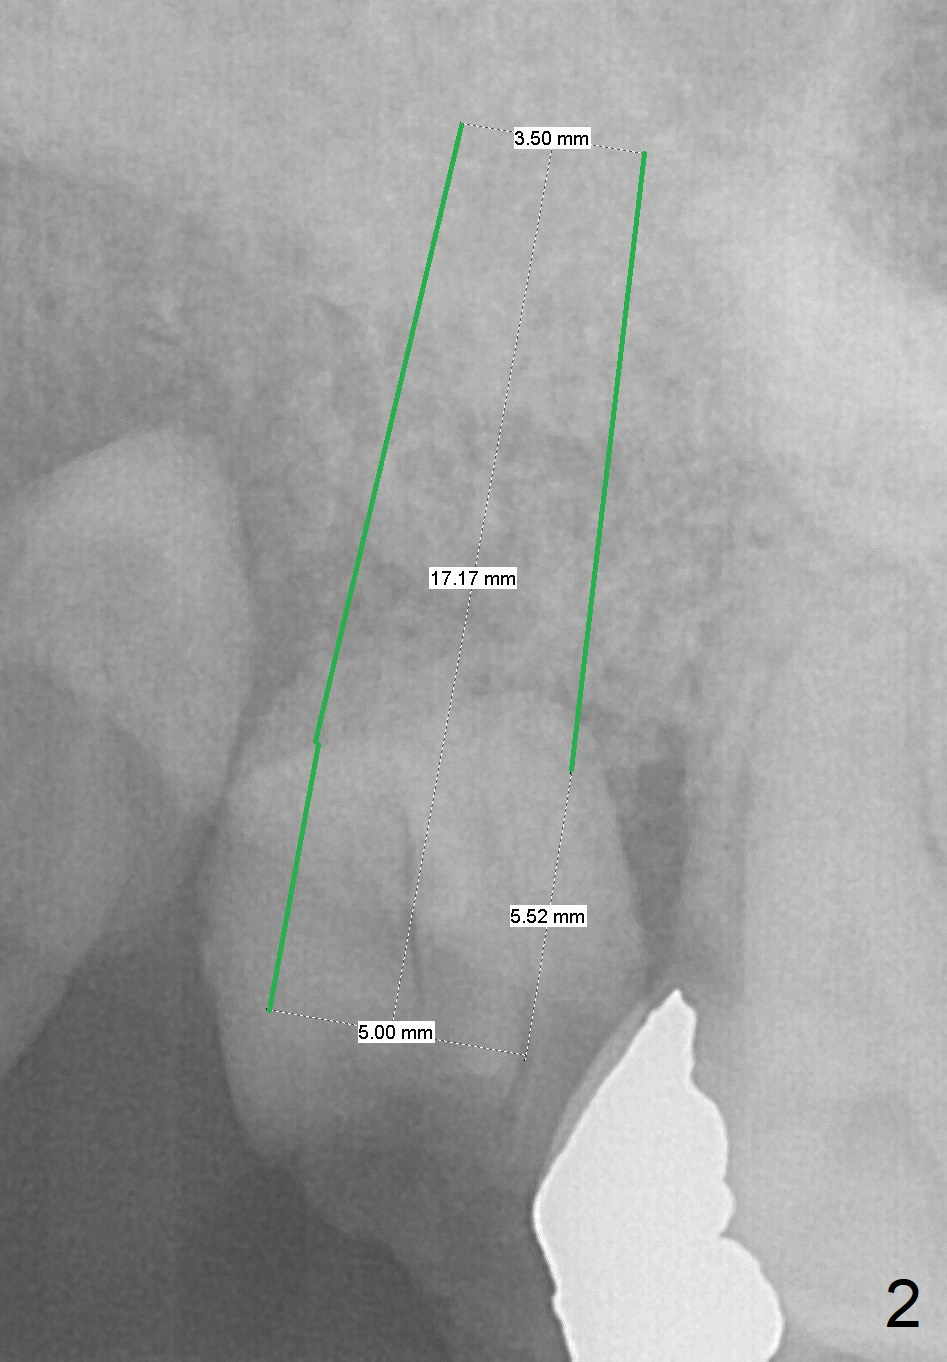

A 60-year-old woman requests extraction of the upper right 2nd and third molars and one implant (Fig.1). Although there is no problem of bone height, the intermaxillary vertical space is limited (data not shown). After implant (Fig.2) and abutment placement, the opposing tooth may need heavy reduction. Pay attention to implant trajectory so that a straight abutment will be used to avoid restorative complication (screw loosening).